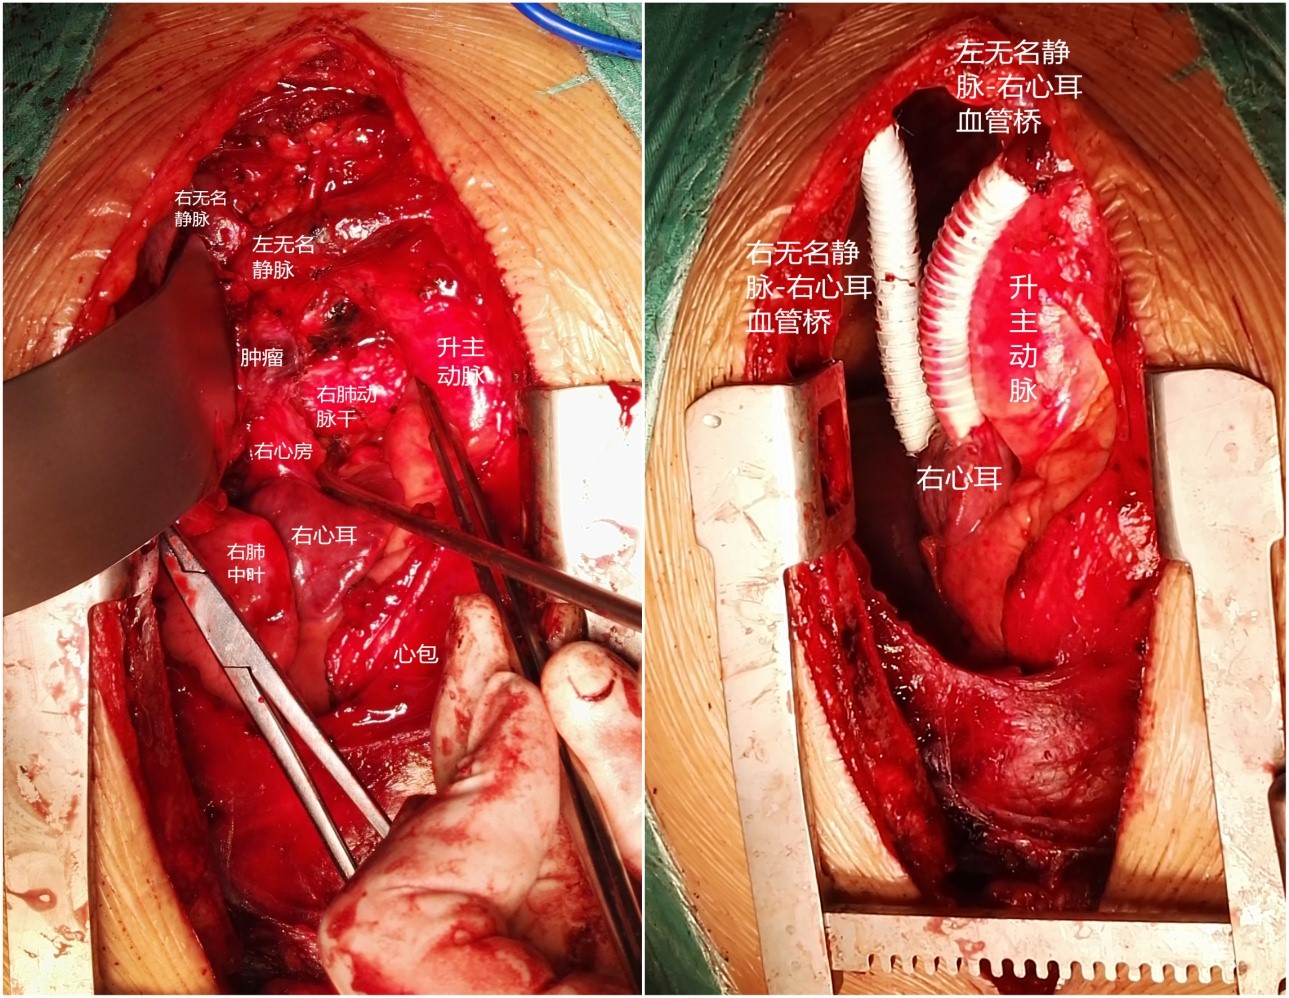

手术采用胸骨正中切口,进胸后细致分离肿瘤与胸骨间粘连,充分探查后可见肿瘤侵及肺门、左右无名及上腔静脉、右心房、心包及纵隔胸膜。陈东红主任认为为达到R0切除,需进行右全肺、上腔静脉切除,人工血管重建。材料采用Gore-Tex带环人工血管,先以人工血管建立左无名静脉-右心耳血管桥,进一步心包内切除右全肺及受肿瘤侵犯的部分右心房,手工牢固缝合右心房,整块切除肿瘤后搭右无名静脉-右心耳血管桥。进一步彻底清扫纵隔淋巴结。完成手术后可见人工血管充盈,心脏搏动有力,血液动力学指标平稳。切除肿瘤标本直径约8cm,手术时间约7小时。